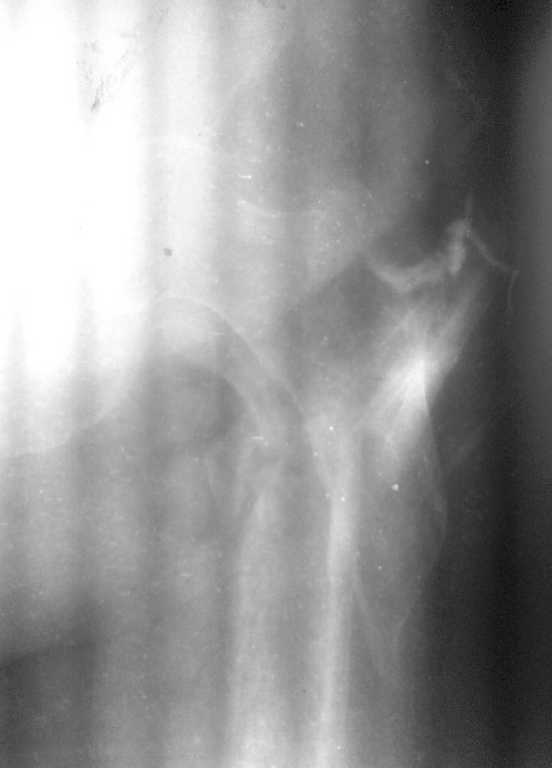

Сразу прошу прощения за качество фистулограммы... лучшего качества не можем добиться.

Фистула функционирует от случая к случаю - последние 2 дня выделений небыло, сделали контрастирование (с трудом вошло 5 мл контраста). Признаков воспаления в зоне поражения нет, лабораторные показатели в пределах нормы. Судя по распростарнению контраста - локальный остеомиелит в месте расположения стержня АВФ